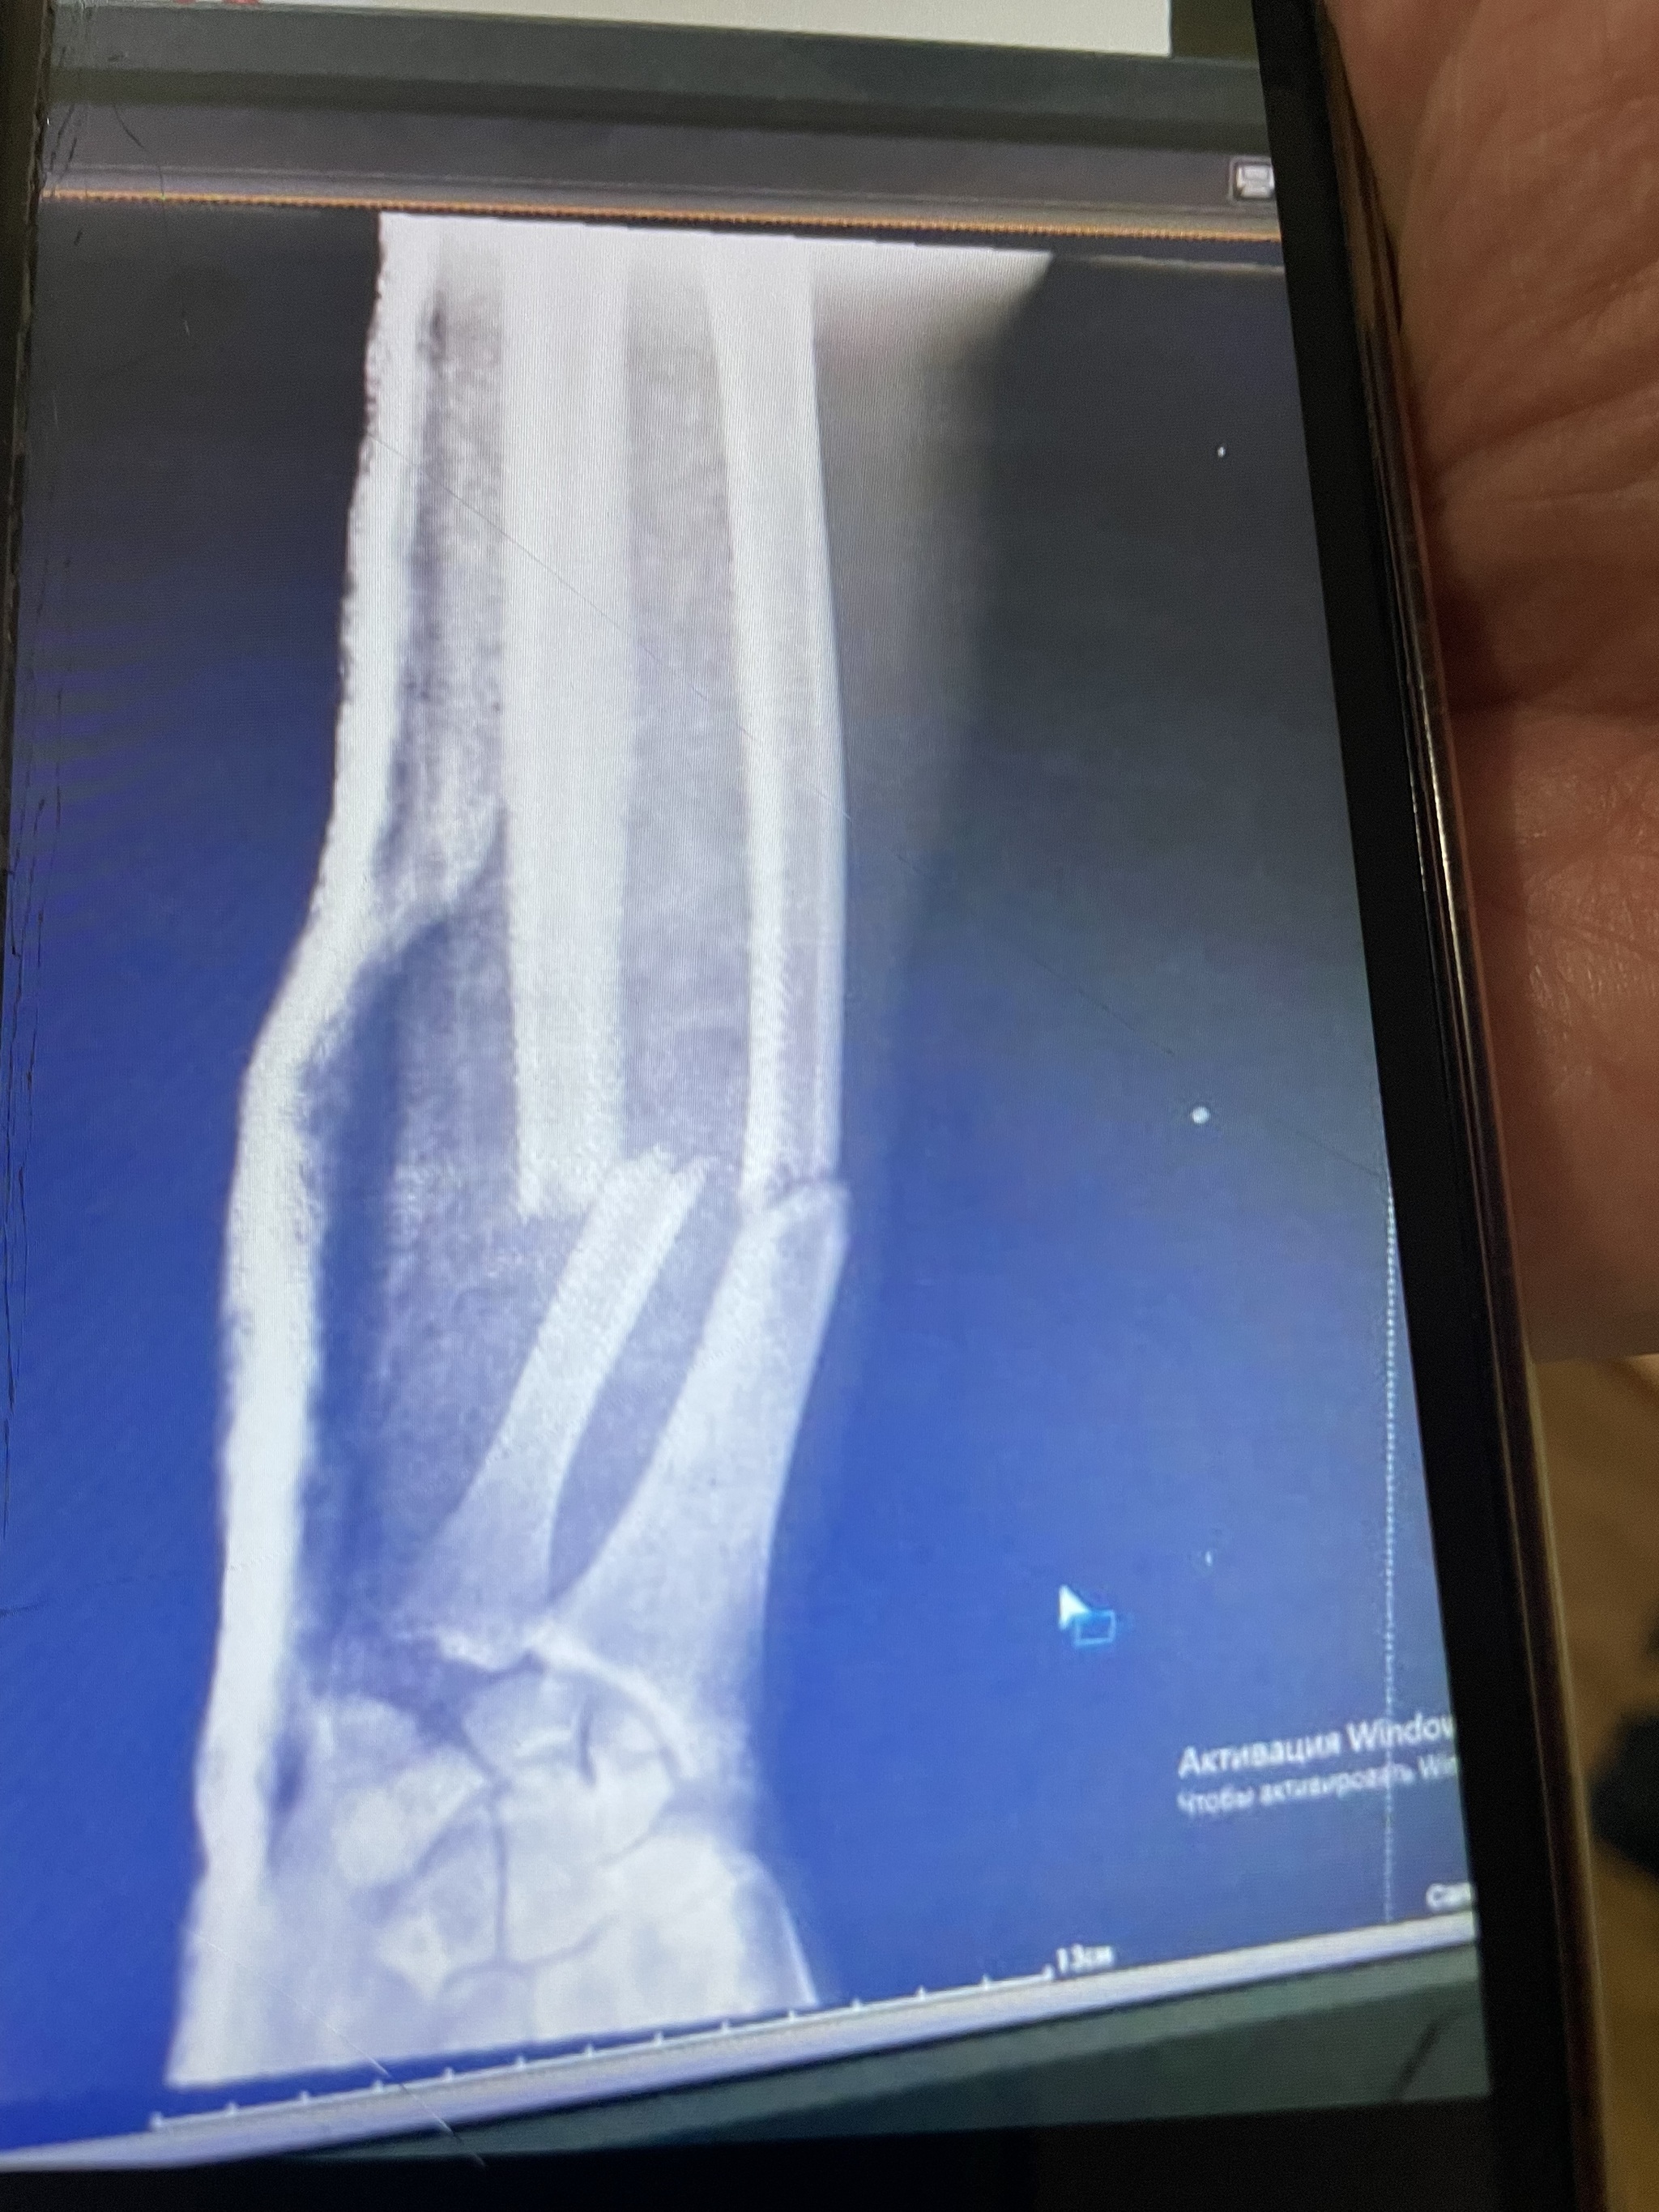

За это время я жил, ел, пил (да-да,бывало не только воду), умудрился практически остаться без руки, благодаря инструктору пр горным лыжам в Архызе (это отдельная занимательная история),

проходил реабилитацию, восстановился, и закрепил вот такую форму: